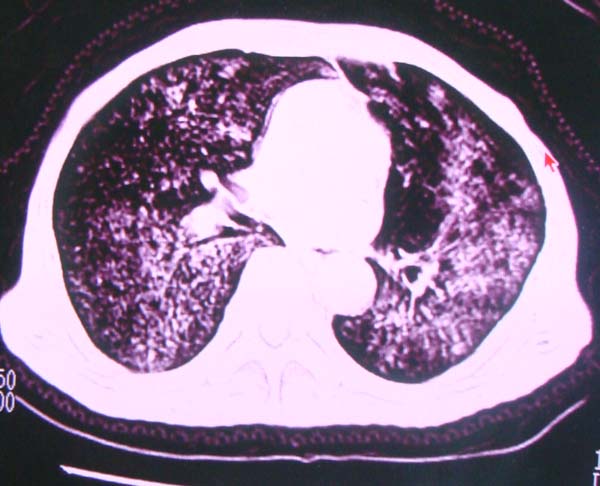

以下是引用zhangzhongshou在2008-2-15 22:25:00的发言:[br]片子照得不清,基本考虑1、细支气管肺泡癌2、亚急性血行播散型肺结核。请结合临床。片子细节显示不清,无法提供进一步意见。

以下是引用杀毒软件在2008-2-15 22:34:00的发言:[br]小叶中心性肺气肿。两肺弥漫性病变,肺泡微石病,过敏性肺炎,尘肺2期,特发性肺纤维化都有可能。[br]不象肺泡癌。